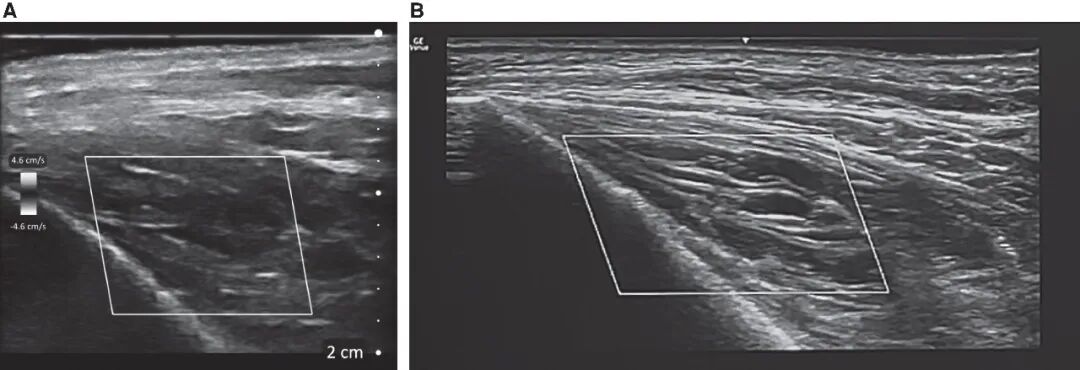

图1. 超声图像示透明质酸填充剂沿SMAS筋膜平面,从鼻唇沟区(A)向眶下区(B)走行,直观呈现了填充剂沿最小阻力路径、经解剖平面发生的移位。

超声可为上述复杂机制提供重要影像学参考,高频超声成像可清晰显示:填充剂分布呈不均质性,即便非刻意注射,也常出现肌内置入现象;填充剂可沿筋膜或肌肉平面发生间室内弥散;且经透明质酸酶干预后,超声回声信号物质仅部分消减,而非完全消失。上述结果提示,酶解效果存在多样性差异,并非呈现「完全溶解 / 未溶解」的二元对立结局。

然而,超声发现仅为描述性而非确定性的,且回声模式不具备特异性——低回声区域可能代表残留透明质酸、水肿或积液,而纤维化通常呈高回声,可能部分遮挡下方的填充剂。陈旧性填充剂往往会产生混合回声,需要结合临床背景进行解读,且图像的采集与解读高度依赖操作者。设备质量也存在很大差异:与低分辨率的手持超声设备相比,高频医用超声系统(15–22MHz)可提供更优异的轴向分辨率与侧向分辨率;手持设备可能难以区分填充剂与水肿、深部脂肪或肌肉等邻近低回声结构,也可能无法清晰显示细微的纤维化改变。目前,业内尚无针对“完全清除”的统一超声诊断标准,因为即便临床外观已得到改善,残留凝胶、水肿与纤维组织增生仍可能同时存在(图3,视频1、视频2)。